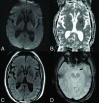

Background and purpose: Mechanical thrombectomy for patients with acute ischemic stroke with tandem occlusions has been shown to present varying reperfusion successes and clinical outcomes. However, the heterogeneity of tandem occlusion etiology has been strongly neglected in previous studies. We retrospectively investigated patients with acute ischemic stroke atherothrombotic tandem occlusion.

Materials and methods: All consecutive patients with acute ischemic stroke with atherothrombotic tandem occlusions treated with mechanical thrombectomy in our center between September 2009 and April 2015 were analyzed. They were compared with patients with acute ischemic stroke with dissection-related tandem occlusion and isolated intracranial occlusion treated during the same period. Comparative univariate and multivariate analyses were conducted, including demographic data, safety, and rates of successful recanalization and good clinical outcome.

Results: Despite comparable baseline severity of neurologic deficits and infarct core extension, patients with atherothrombotic tandem occlusions were older (P < .001), were more frequently smokers (P < .001), and had globally more cardiovascular risk factors (P < .001) than the other 2 groups of patients. The patients with atherothrombotic tandem occlusions had significantly longer procedural times (P < .001), lower recanalization rates (P = .004), and higher global burden of procedural complications (P < .001). In this group, procedural complications (OR = 0.15, P = .02) and the TICI 2b/3 reperfusion scores (OR = 17.76, P = .002) were independently predictive factors of favorable clinical outcome.

Conclusions: Our study suggests that atherothrombotic tandem occlusions represent a peculiar and different nosologic entity compared with dissection-related tandem occlusions. This challenging cause of acute ischemic stroke should be differentiated from other etiologies in patient management in future prospective studies.